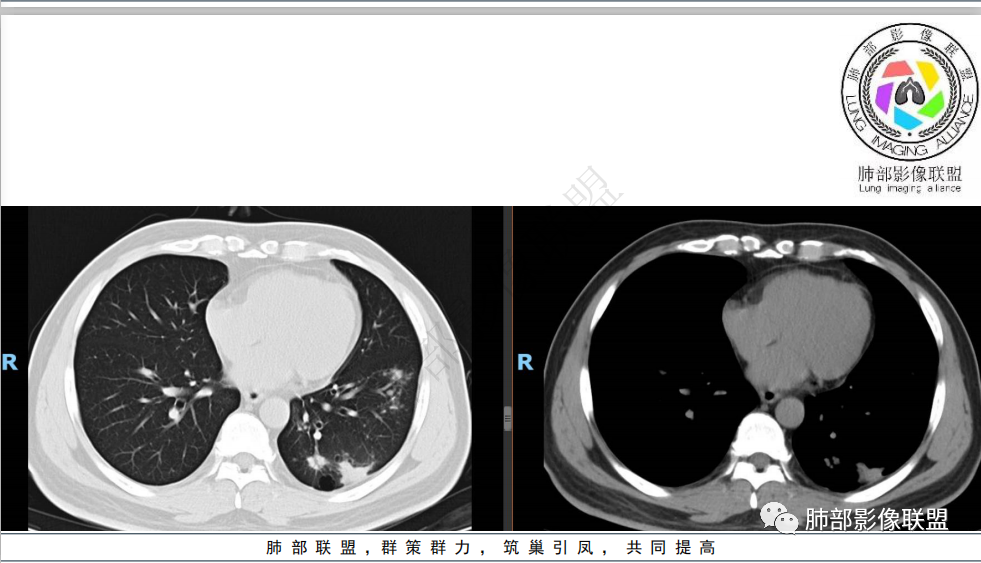

双肺胸膜下多发大小不等结节,部分以血管束周围分布,形态不规则,边缘收缩,部分可见融合,体检发现,考虑隐球菌,结核,腺癌。

中年男性,体检发现肺部病变,辅查指标未见异常。影像学表现为左肺下叶多发结节及树芽,较大结节位于胸膜下区,临近胸膜增厚,胸膜下脂肪间隙清晰。考虑感染性病变,首先考虑结核,是否胸膜下区为隐球菌,待排,建议还是完善增强检查。

左肺胸膜下多发结节及斑点状影,邻近肺野见树芽征,大结节边界平直,有近端充气支气管征,小结节支气管贯通,粗细不均,边缘见长毛刺,周围见卫星灶,综和考虑支持炎性肉芽肿,一元考虑隐球菌,二元考虑隐球菌并TB

中年男性,有吸烟史,查体发现,实验室检查无明显异常。左下肺背段实变影,边缘平直收缩,边界清,基底段多发结节影,实变影,密度高,边缘平直收缩,支气管穿过,有牵拉性条索影、支气管扩张等,考虑肺结核可能性大。左肺下叶背段病灶若是一元论也考虑结核,腺癌不排除。

体检患者,无典型临床症状,也无确切免疫缺陷。左肺下叶结节及实性密度斑片影,边界较清楚,簇状分布趋势,部分边缘平直,总体上符合肉芽肿性病变影像学改变。常见病变为继发性肺结核及隐球菌感染等。如左肺下叶节点影符合气道“树芽”则支持继发性肺结核诊断,且有好发部位,上叶及下叶背段。隐球菌同样可表现为多形性,通常有孤立肉芽肿型、肺炎实变型、混合型(多发结节/实变/空洞)。病灶散落胸膜下,密度偏柔和,磨玻璃晕,“葫芦兄弟”“蘑菇兄弟”通常是隐球菌感染典型表现。所以综合临床及影像表现,综合考虑隐球菌>结核。